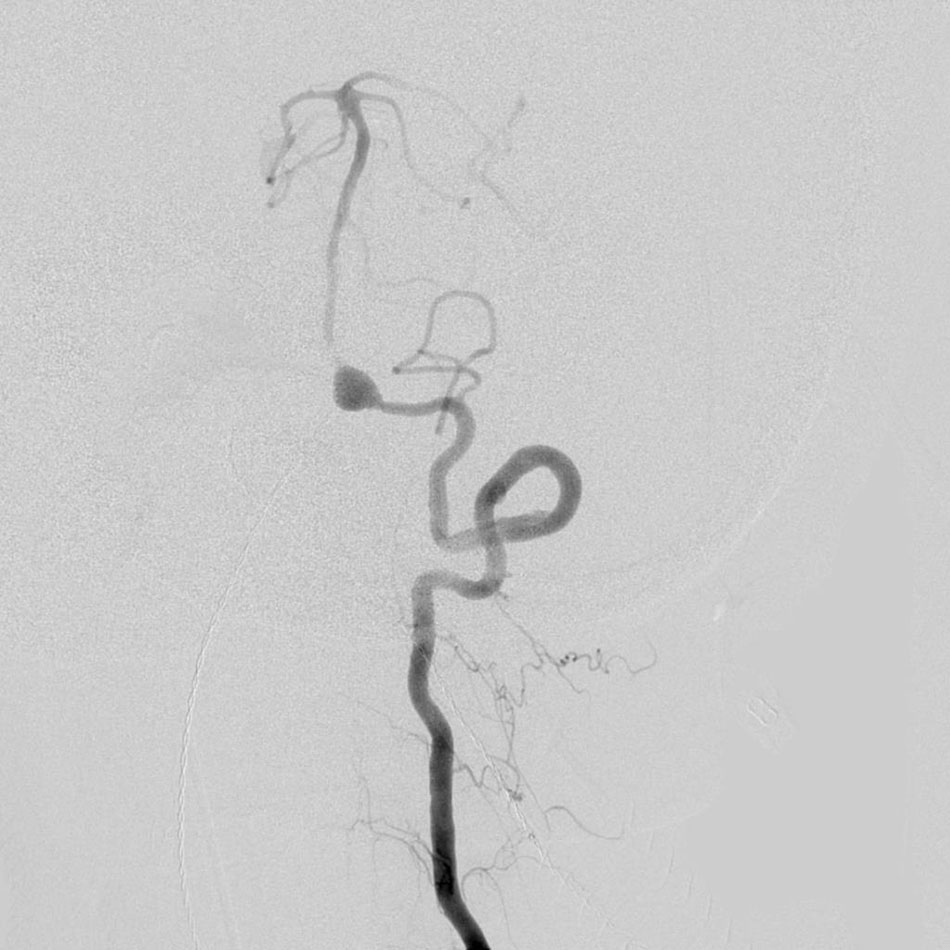

An aneurysm is an abnormal ballooning out of an artery. This occurs when there is a weakening in the wall of the artery and this puts a patient at risk of rupturing or bleeding from the aneurysm. Bleeding from an aneurysm represents a serious medical problem that can cause subarachnoid haemorrhage and is a frequent cause of haemorrhagic stroke.

Aneurysms usually form over time. The average age when a person has symptoms from an aneurysm is usually 40-60 years old, although this can be quite variable. It may be associated with other medical conditions like hypertension and with a history of smoking. About 20% of patients with aneurysms will have multiple (two or more) aneurysms at the same time.

Many patients have no symptoms until the aneurysm ruptures. In some cases, aneurysms can cause headaches or neurologic symptoms before bleeding. Some aneurysms are found prior to breaking or bleeding using CT scanner or MRI. Most people with aneurysms need a cerebral angiography for definitive diagnosis and to determine the best treatment.

The treatment goal with aneurysms is to close off the aneurysm, thereby eliminating the chance of bleeding. This can be done with a surgical procedure to “clip” the aneurysm or an endovascular procedure to “coil” the aneurysm. Clipping an aneurysm is done by opening the skull and placing a clip over the aneurysm.

Endovascular treatment of aneurysmsis a technique which greatly benefits patients with serious medical conditions who are unable to sustain the stress of surgery. Platinum coils are guided into the aneurysm via a catheter, creating a clot that effectively closes the aneurysm off from the surrounding circulation, preventing the risk of haemorrhagic stroke in the future.

Larger aneurysms with wider necks or openings are sometimes treated with other endovascular techniques using a balloon to help keep the coils in position inside the aneurysm, or a small stent, which is a small mesh tube that can keep the coils in place.